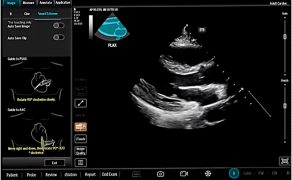

Proces ten rozpoczyna się już na etapie akwizycji obrazu. Algorytmy sztucznej inteligencji coraz częściej pełnią funkcję systemów prowadzenia użytkownika, pomagając w prawidłowym ustawieniu głowicy, doborze optymalnej projekcji oraz stabilizacji obrazu. Ma to szczególne znaczenie w warunkach intensywnej terapii i bloku operacyjnego czy szpitalnego oddziału ratunkowego, gdzie badania POCUS wykonywane są często w pośpiechu, w nieidealnych warunkach sonoanatomicznych i organizacyjnych. Dzięki temu możliwe staje się uzyskanie diagnostycznie użytecznych obrazów również przez lekarzy z mniejszym doświadczeniem ultrasonograficznym, bez obniżenia jakości badania (6).

Kolejnym krokiem jest automatyczna identyfikacja struktur anatomicznych oraz wykonywanie złożonych pomiarów, które dotychczas wymagały wysokiej biegłości technicznej. W praktyce klinicznej obejmuje to m.in. automatyczną ocenę funkcji skurczowej serca, analizę przepływów, ocenę zmienności wymiarów naczyń czy identyfikację charakterystycznych artefaktów płucnych. Z punktu widzenia anestezjologii i intensywnej terapii kluczowe znaczenie ma fakt, że pomiary te wykonywane są szybko, powtarzalnie i w sposób ustandaryzowany, co znacząco ogranicza zmienność między operatorami i poprawia bezpieczeństwo podejmowanych decyzji (4).

Jednym z najbardziej przełomowych elementów tej transformacji jest rozwój systemów automatycznego labelingu, czyli kolorowego kodowania struktur anatomicznych w czasie rzeczywistym. Rozwiązania te, oparte na algorytmach uczenia maszynowego i głębokich sieciach neuronowych (m.in. architekturze U-Net), umożliwiają automatyczne rozpoznawanie i oznaczanie kluczowych struktur, takich jak nerwy, naczynia, mięśnie, powięzi czy opłucna, przy użyciu czytelnego kodu kolorystycznego. W efekcie obraz ultrasonograficzny przestaje być jedynie płaską reprezentacją anatomii, a zaczyna pełnić funkcję interaktywnego interfejsu informacyjnego (6).

Z perspektywy anestezjologii szczególne znaczenie ma zastosowanie labelingu w regionalnych technikach znieczulenia oraz w procedurach wykonywanych pod kontrolą ultrasonografii. Kolorowe oznaczenie struktur pełni wówczas funkcję swoistego head-up display, który w czasie rzeczywistym wspiera orientację przestrzenną operatora i zmniejsza ryzyko przypadkowego uszkodzenia struktur krytycznych. Badania wskazują, że tego typu rozwiązania mogą skracać czas wykonywania procedur, zwiększać ich bezpieczeństwo oraz zmniejszać zależność jakości zabiegu od doświadczenia operatora (2, 6).

Najistotniejsza zmiana zachodzi jednak na poziomie interpretacji danych. Tradycyjnie ultrasonografia była narzędziem opisowym, a lekarz samodzielnie formułował hipotezy diagnostyczne na podstawie obserwowanego obrazu. Współczesne systemy AI przesuwają ten proces w kierunku interpretacji wspomaganej algorytmicznie, w której obraz ultrasonograficzny integrowany jest z innymi danymi klinicznymi i prezentowany w postaci sugestii diagnostycznych, trendów lub wskaźników istotnych klinicznie. Sztuczna inteligencja porządkuje dane i zmniejsza obciążenie poznawcze lekarza, nie przejmując jednak odpowiedzialności za decyzję (2, 3, 7).